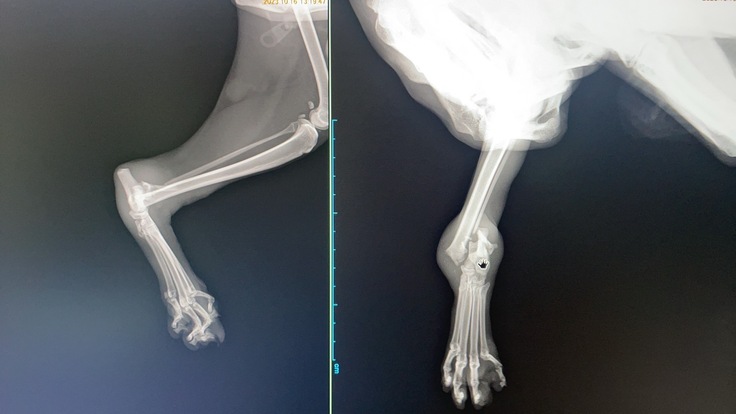

そこに来て10月に罠による断脚被害での保護がメディアに取り上げられると他の地域からも「近所にもケガをした猫がいるから助けてあげて」などの相談が相次ぎました。